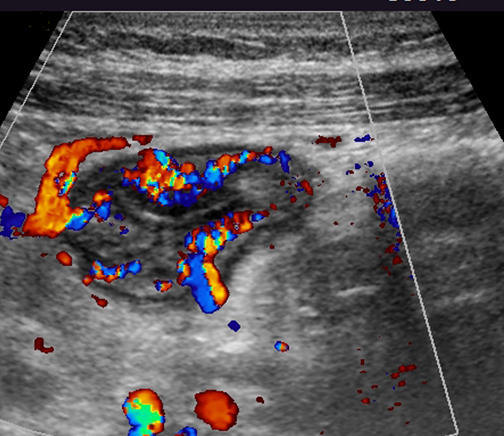

Colour Doppler images showing hyperermia of the bowel

Additional Colour Doppler images show hyperermia of the bowel